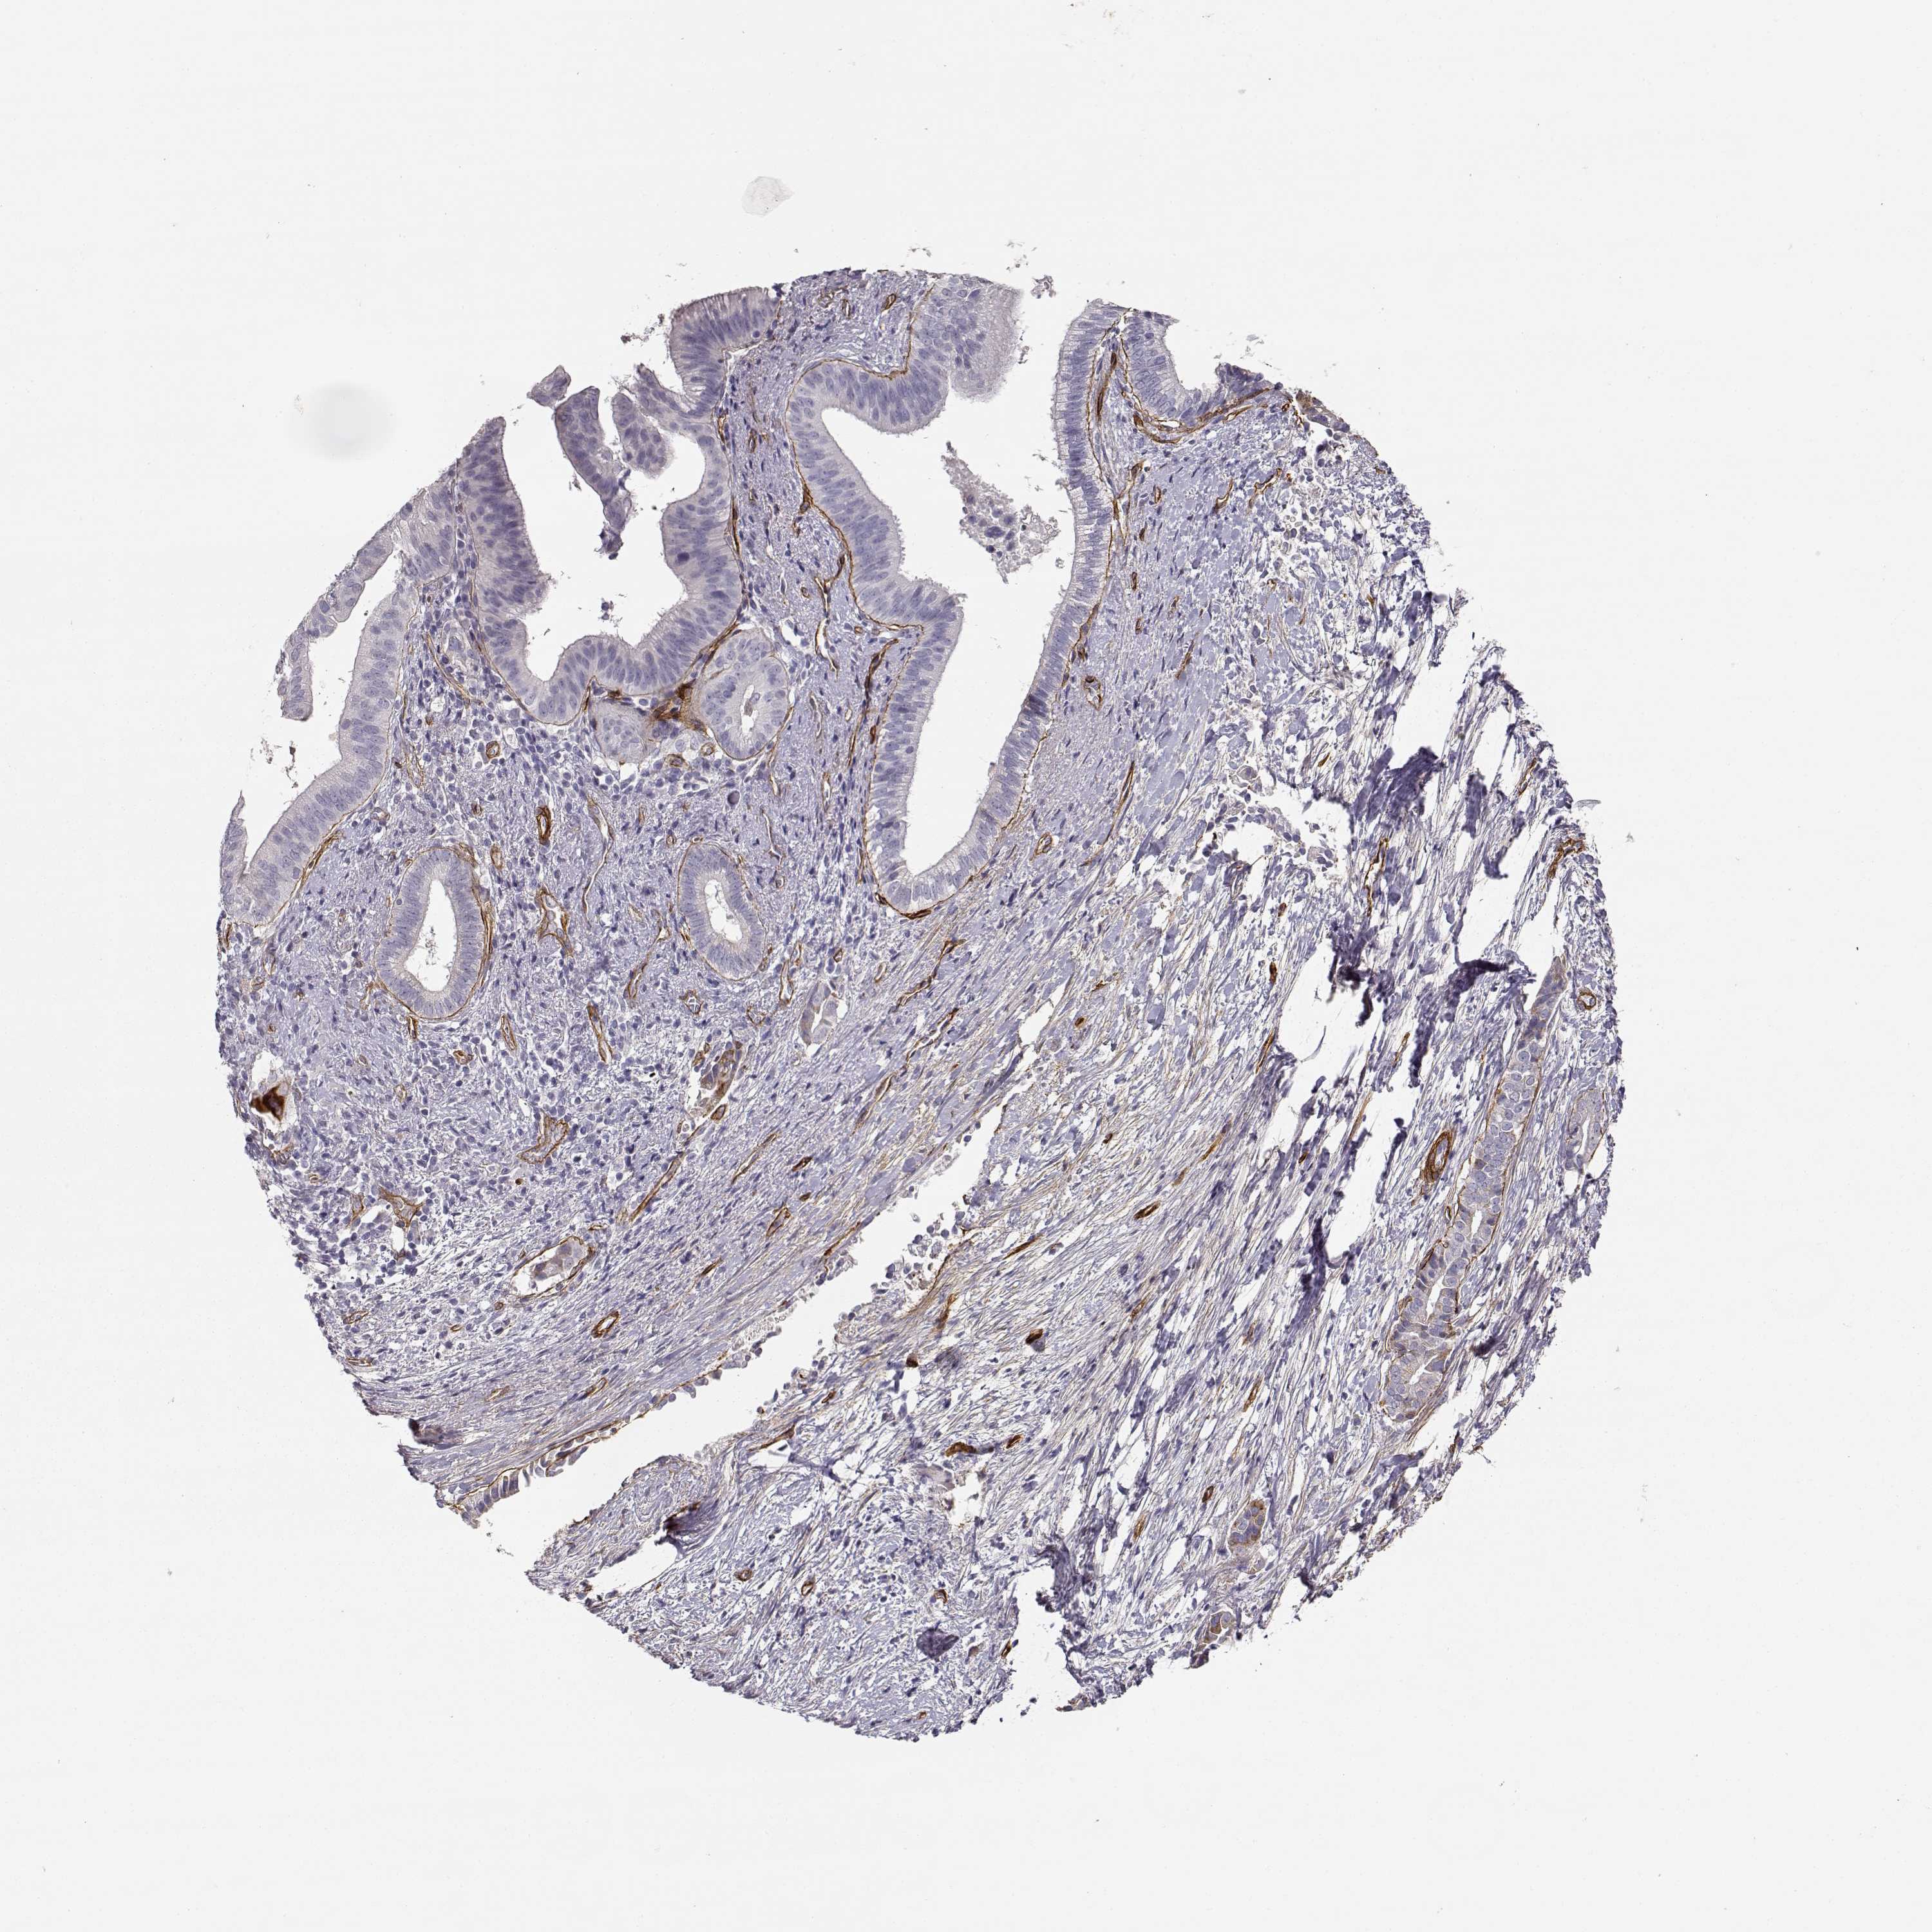

PANCREATIC CANCER - Protein expressioni

A mouse-over function shows sample information and annotation data. Click on an image to view it in a full screen mode. Samples can be filtered based on level of antibody staining by selecting one or several of the following categories: high, medium, low and not detected. The assay and annotation is described here.

Note that samples used for immunohistochemistry by the Human Protein Atlas do not correspond to samples in the TCGA dataset.

Antibody stainingi

Antibody staining in the annotated cell types in the current human tissue is reported as not detected, low, medium, or high, based on conventional immunohistochemistry profiling in selected tissues. This score is based on the combination of the staining intensity and fraction of stained cells.

Each image is clickable and will lead to virtual microscopy that enables deeper exploration of all samples and also displays staining intensity scores, fraction scores and subcellular localization as well as patient and tissue information for each sample.

Antibody HPA001908

Antibody HPA001909

Antibody CAB004486

Antibody CAB078163

Adenocarcinoma, NOS

Adenocarcinoma, metastatic, NOS